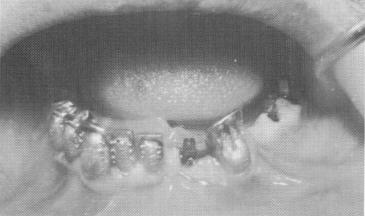

Another patient helped by the combined implant procedure is shown in Fig. 13-33. Here the patient, who had only a few remaining mandibular anterior teeth, was afflicted with a poorly functioning, re-movable, bilaterally free-end saddle partial denture. Endodontic root stabilizers were used to help stabi-

1 Castings set on abutment teeth & ventplants set into osseous structure